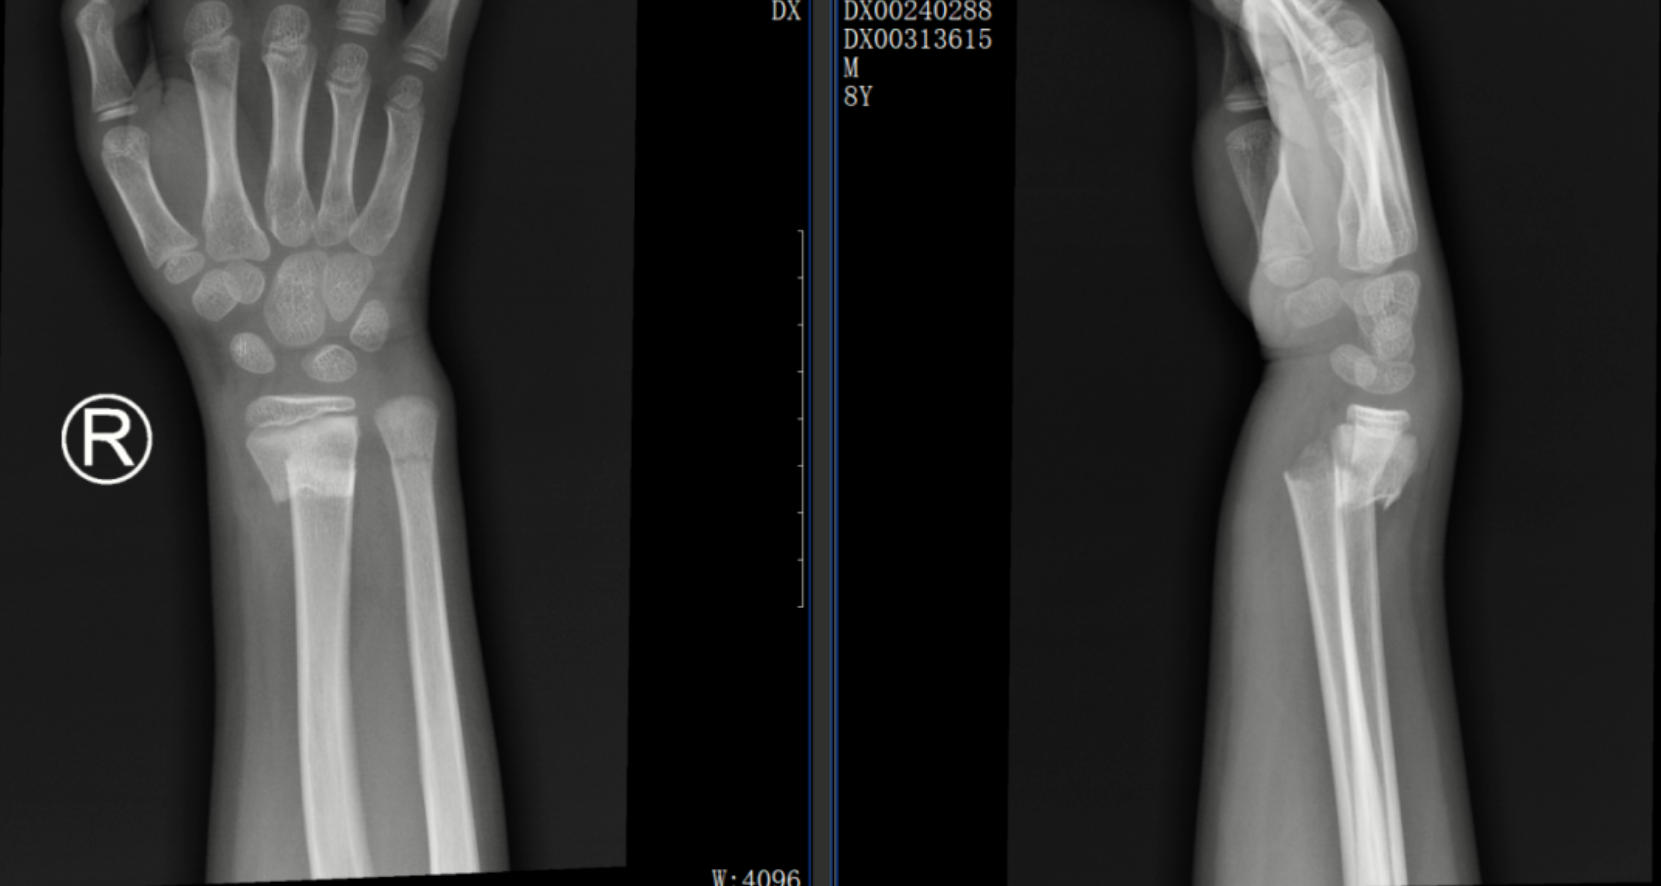

一位 8歲的學(xué)生在上學(xué)途中不慎摔傷,造成尺橈骨遠(yuǎn)端骨折。家屬心急如焚,為保守治療來到了我院中醫(yī)正骨中心就診。中醫(yī)正骨醫(yī)師運(yùn)用精湛的手法為小朋友進(jìn)行了復(fù)位,并配合夾板固定。3 周后骨痂形成,小朋友的功能活動(dòng)也恢復(fù)良好。這一案例,讓家其屬深刻體會到了中醫(yī)正骨的獨(dú)特魅力。

正骨前后影像資料